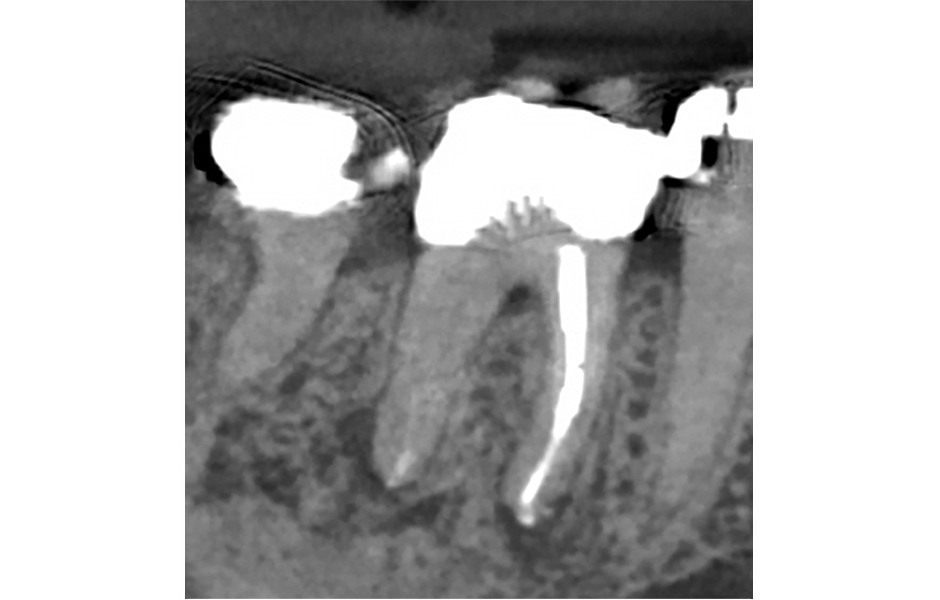

Pro radiologickou diagnostiku byl pořízen periapikální (PA) rentgenový snímek (obr. 1) a CBCT snímek s omezeným zorným polem (obr. 2a–d). Předchozí endodontické ošetření zahrnovalo zaplnění tří kanálků s nedostatečnou hustotou výplně v apikální třetině meziálních a distálních kořenů. V oblasti apexů meziálních (3 × 3 mm) a distálních (3 × 5 mm) kořenů byla patrná periapikální projasnění. CBCT (obr. 2a–d) potvrdilo nezaplněný distolingvální (DL) kanálek a možný střední meziální (MM) kanálek; koronální CBCT řez meziálního kořene (obr. 2c) také naznačuje přítomnost apikální delty spíše než jediného apikálního foramenu. Nebyly zjištěny žádné známky prasklin či fraktur.

Obr. 2a, b: Předoperační CBCT řezy zubu 46 – a) sagitální, b) axiální.

Obr. 2c, d: Předoperační CBCT řezy zubu 46 – c) meziální kořen, d) distální kořen.